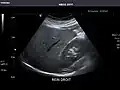

Abdominal Ultrasound (Full Exam)

STRUCTURED REPORT

(Technique: Transabdominal ultrasonography; Device: Toshiba Aplio XG)

Liver: Diffusely homogeneous and normal in echogenicity. No focal mass or contour nodularity. No intrahepatic biliary ductal dilatation.

Portal Vein: Patent main portal vein.

Gallbladder: No stones, wall thickening, or pericholecystic fluid.

Common Bile Duct: Nondilated measuring 1.3 mm at the level of the porta hepatis.

Pancreas: Visualized portions unremarkable.

Spleen: Normal in size.

Kidneys: Right and left kidneys measure 11.5 cm and 12 cm in length respectively. No hydronephrosis. Small left lower pole kidney cyst.

Ascites: None.

Aorta: Visualized portions normal in caliber, 16 x 15 mm.

IVC: Normal.

IMPRESSION:

Normal abdominal ultrasound.